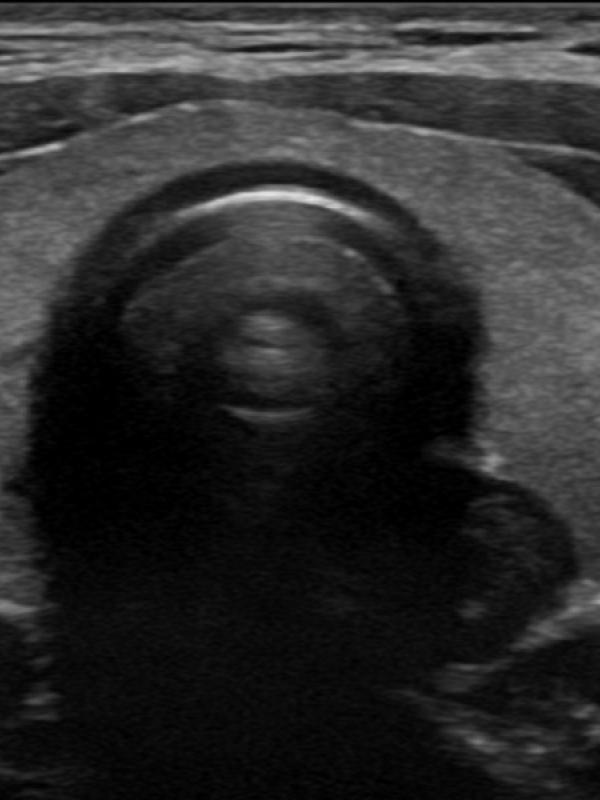

Scrotal ultrasound

Ultrasound imaging is the primary diagnostic modality used to evaluate the scrotum/testicles. Referring providers will order a scrotal ultrasound for a number of reasons. The most common reasons are: testicular pain, a lump is discovered, or if a hernia is suspected. Undescended testis.

Scrotal ultrasound FAQ

- Will the ultrasound of the scrotum and testicles be painful? No. The ultrasound exam will not be painful at all. The sonographer uses warm ultrasound gel and very light pressure from the transducer to image the testicles and scrotal contents.

- Is there any preparation required for a scrotal ultrasound exam? No, there is no preparation needed before having a scrotal ultrasound.